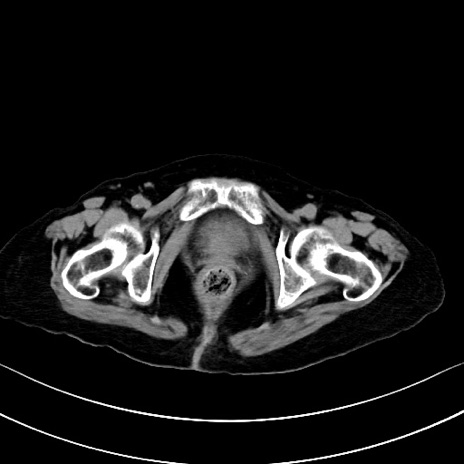

横断像

他院CT